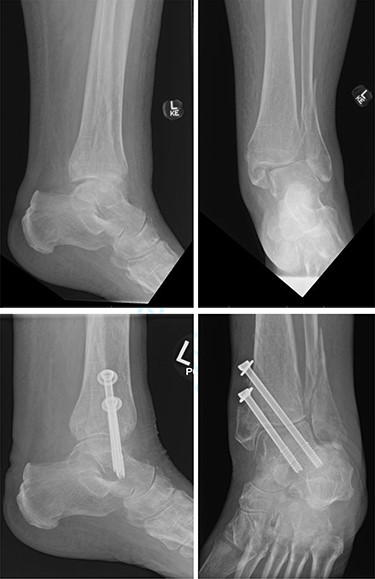

One patient (16.7%) with a bimalleolar (posterior and medial malleoli involvement) fracture had evidence of minor talar shift at 5 months, but no other significant radiological findings. Additionally, the patient reported no pain, and mobility recovered to a preoperative level (Fig. 3).

Top—Bimalleolar ankle fracture with talar shift. Bottom—Radiograph at 5 months showing small amount of talar shift.